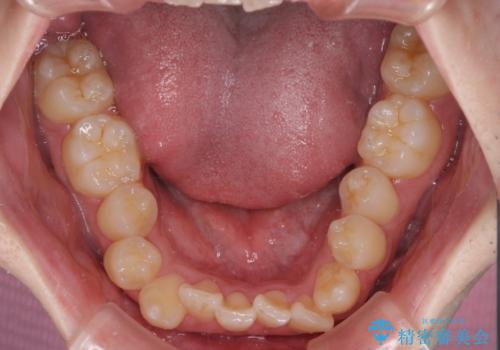

全顎的なクロスバイト 補助装置を用いてワイヤー矯正

前歯のクロスバイトや八重歯の他に、左右最後臼歯のシザーズバイト(鋏状咬合)が認められました。

シザーズバイト改善のために補助装置を使用しながら、ワイヤー装置にて全体の歯列を整えることとしました。